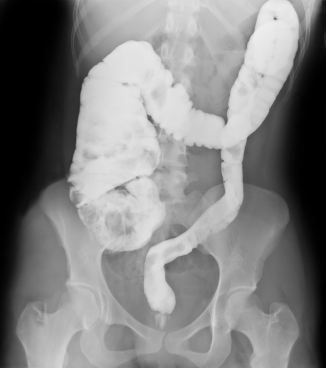

ДИАГНОСТИКА

Изучение истории болезни и медицинский осмотр не проводятся. Изображениями исследования проводятся для установления диагноза.

Медицинские процедуры, проводимые при заболевании кишечные заворот кишок (скручивание кишечника): Биохимический анализ крови, Клинический анализ крови, Спиральная компьютерная томография, Ферменты. Липаза, Анализ мочи, РентгенЛЕЧЕНИЕ И ПРОФИЛАКТИКА